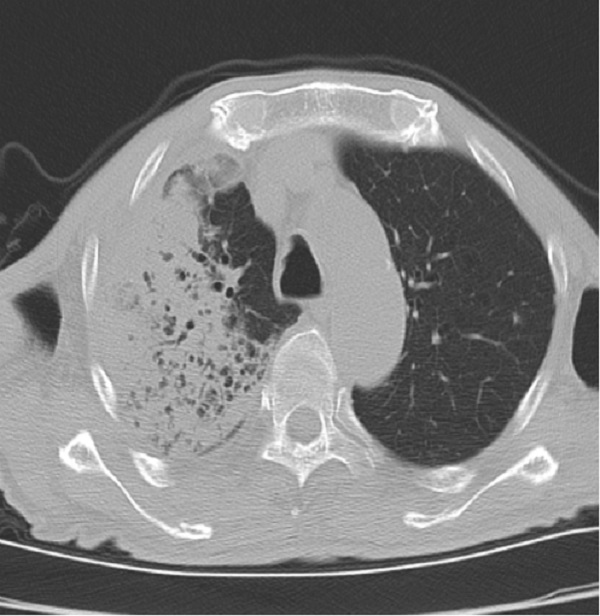

许爷爷今年83岁,不慎摔伤致左髋部疼痛入住陕健医二一五医院骨五科,完善检查发现许爷爷新冠病毒检测为阳性,肺部已有感染。由于年事已高,有基础病且合并新冠病毒感染,病情复杂危重,情况非常棘手。骨五科潘建宏主任团队为许爷爷进行了全面细致的病情评估,并请院内相关专家组会诊,制定了有针对性的治疗方案。

入院一周后,肺部感染逐渐得到控制,氧饱和度正常后,潘主任团队为许爷爷进行左侧人工股骨头置换术,手术十分顺利。术后,科室医护人员密切关注老人的神志、呼吸和各项生命体征变化,及时根据病情变化调整治疗方案,并加强肺功能锻炼。术后三天,许爷爷能够在助行器辅助下下床行走,无明显不适,生命体征平稳。在科室医护团队日夜精心的照料下,许爷爷日见好转,说话声音开始响亮,浑身也有了力气,其家属表示深深地感谢,经过半个多月的精心治疗,许爷爷现已康复出院。